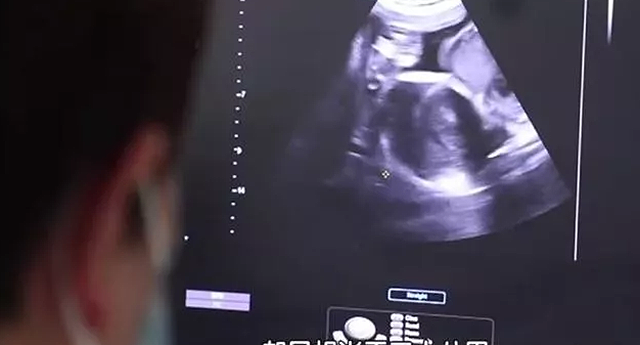

高龄产妇生下三胞胎在梁嘉怀孕第10周时,梁嘉照例到医院检查,可却被医生告知,自己竟然怀了三胞胎,这个概率仅有十万分之一。

这让两人喜出望外,巨大的惊喜笼罩着他们。

可同一时间,梁嘉又考虑到了自己的身体状况,高龄产妇又是多胎妊娠,自己的身体又能否承受得了呢?

可医生却告诉她,三胞胎共用一个胎盘,如果手术失败的话,那么三个孩子都保不住。

随着时间的推移,梁嘉的肚子越来越大,为了保证孩子的健康,两人没有漏过一次产检。

第30周时,医生却告诉梁嘉,胎儿有些偏小,生长速度很慢,即便到了36周,每个孩子的体重也仅有4斤。